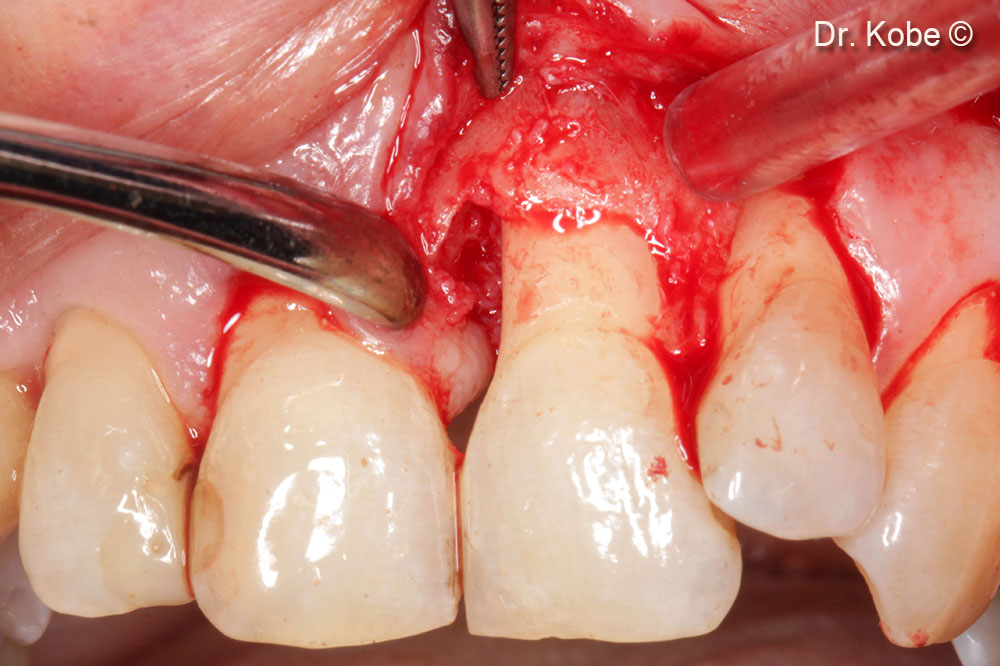

Tiếp cận và làm sạch khu vực bị lỗi